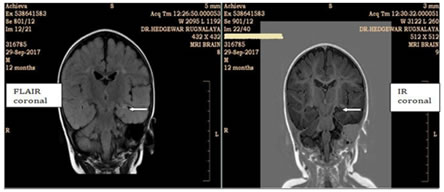

3

Image 3: A case of cystic encephalomalacia with periventricular leukomalacia. T2W axial image shows cystic changes in cortex which are suppressed on FLAIR and paucity of periventricular white matter.

Out of 3 patients with phakomatoses, 2 patients (66.7%) had tuberous sclerosis (TS). 1 patient had Sturge Weber syndrome (SWS). Thus, tuberous sclerosis (TS) was the most common pathology in patients with phakomatoses. Out of 2 patients with inherited metabolic disorders, neuronal ceroid lipofuscinosis and Zellweger syndrome constituted 1 patient (50%) each. Anoxia and HIE was the cause of seizures in 23 patients in our study. Out of them, 7 patients (30.4%) and 16 patients (69.6%) were preterm and term respectively based on the clinical information licited. Theneuro imaging findings in HIE mainly comprised of periventricular leukomalacia, gliosis/encephalomalacia with cystic changes, basal ganglia and thalamic lesion and only subcortical white matter involvement. Most of the patients had multiple findings. Periventricular leukomalacia was the most common finding seen in 17 patients (73.9%) followed by gliosis/encephalomalacia with cystic changes was seen in 13 patients (56.5%). Basal ganglia and thalamic lesion wereseenin9patients (39.1%). Rare finding of only subcortical white matter involvement was seen in only 1patient. Thus, in our study, most commonneuro imaging finding in patients with anoxia and HIE was periventricular leukomalacia